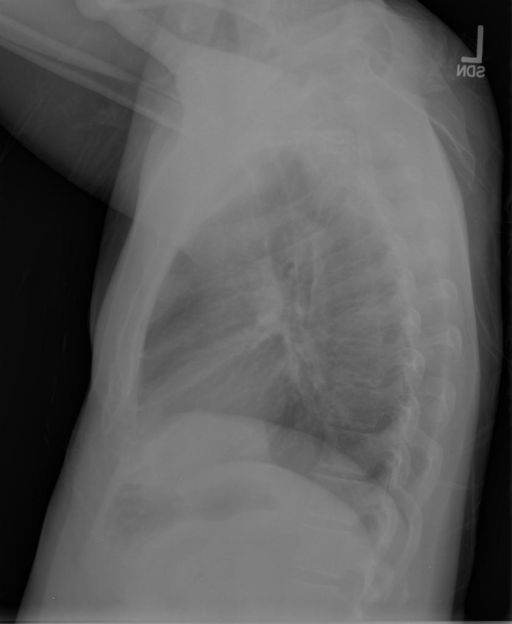

We compare our projected X-Rays with samples from the OpenI dataset for frontal and lateral views in Figure 5. The differences in the frontal view are due to the different positioning of the shoulder girdle. In the X-Rays, the arms are usually placed alongside the body, while in the projected images, the arms are raised due to the nature of the CT scan. In the lateral view, the X-Rays show a more comprehensive range of orientation and pose. However, the projected images, typically taken while the patient is lying down, result in similar poses between the different images. This leads to visual differences between images of female patients in both frontal and lateral views, such as the third column and second row of real X-Ray images and the first column and second row of projected images.